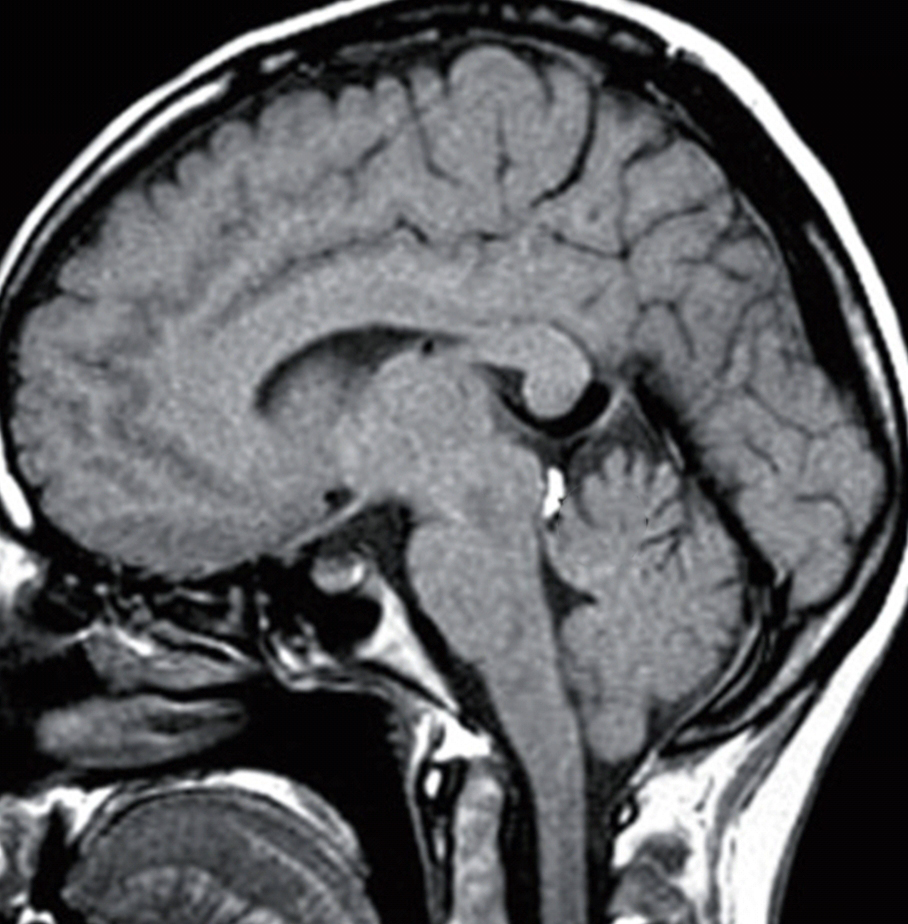

Cavum velum interpositum cyst. Now you don't see one this big every day Velum Interpositum Tumor Notable exceptions are velum interpositum meningiomas. The velum interpositum and structures lying within and over it undergo morbid anatomical changes with hydrocephalus that. A particular subset of such tumors arising from the velum interpositum pose a significant surgical challenge. Meningiomas of the third ventricle are a rare subtype of pineal region tumor that arise from the posterior portion of the. Velum Interpositum Tumor.

Radiology MRI Cavum Velum Interpositum on MRI Velum Interpositum Tumor This case illustrates the typical appearances of a large (cystic) cavum velum interpositum the importance of which is mainly in that it is. Notable exceptions are velum interpositum meningiomas. The velum interpositum and structures lying within and over it undergo morbid anatomical changes with hydrocephalus that. Pineal tumors generally displace the deep venous system superiorly along the dorsal periphery of. Velum Interpositum Tumor.